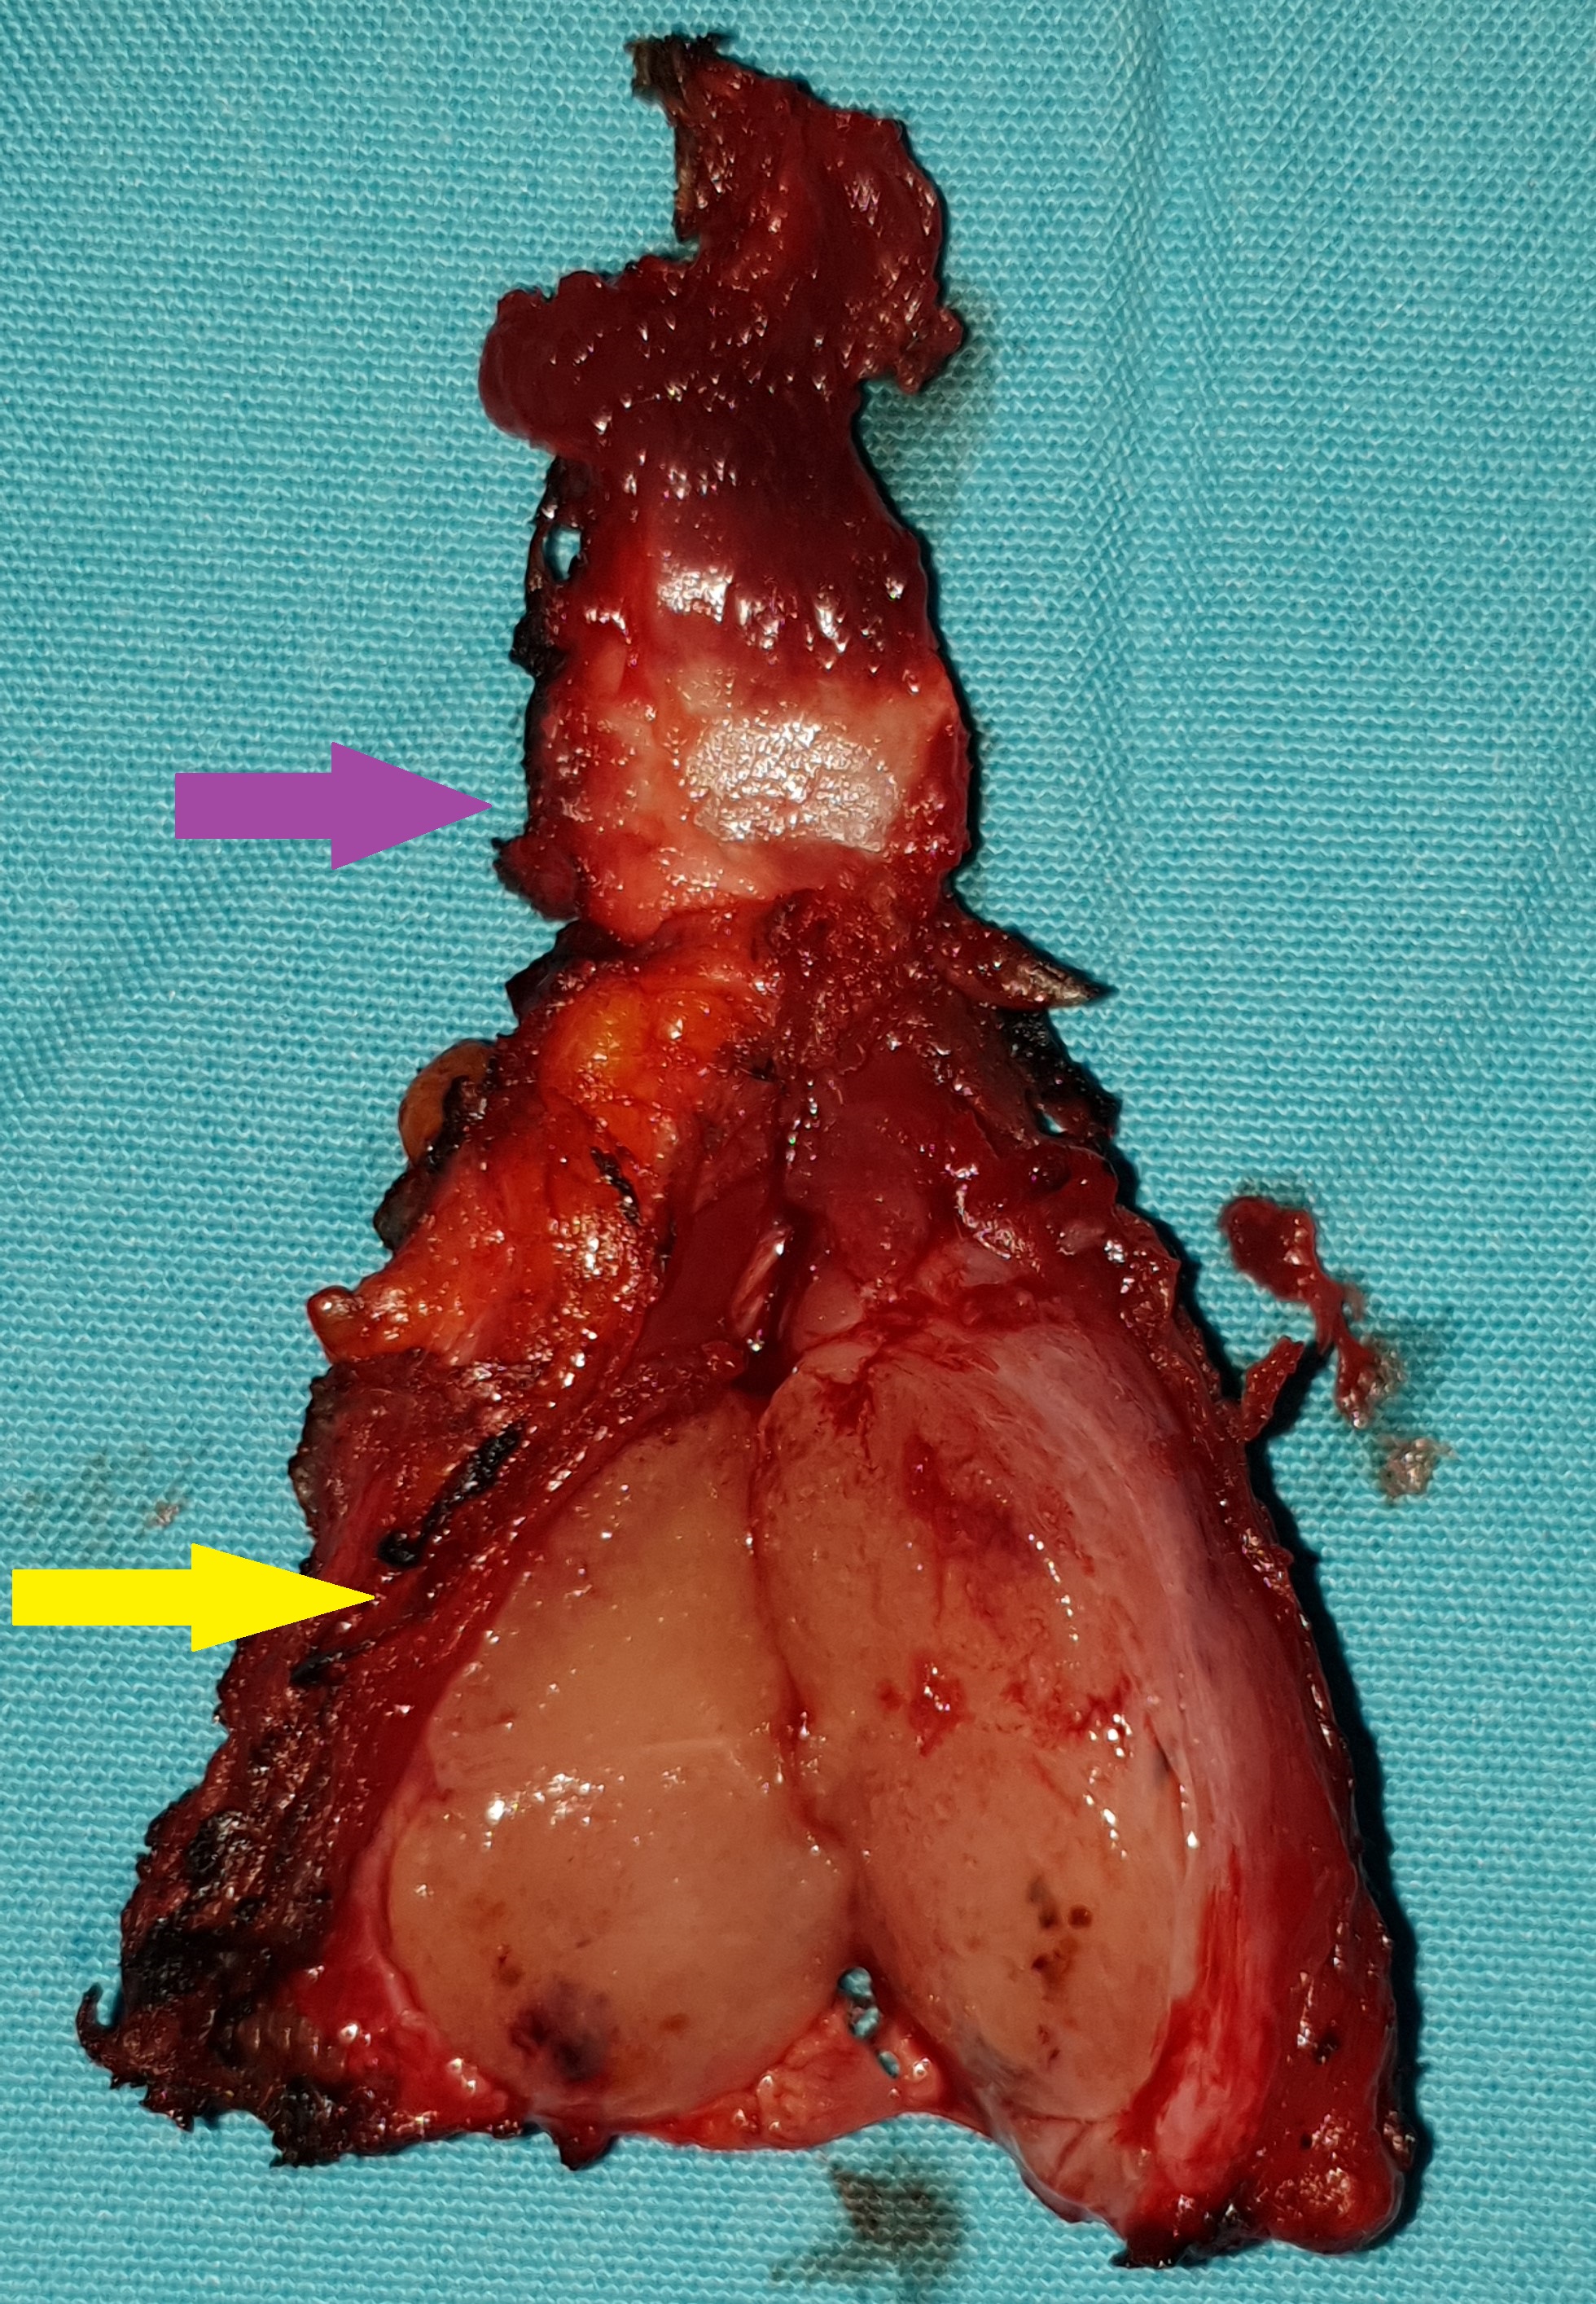

Gross examination of the excised cyst reveals a smooth surface lining of uniform thickness without papillary projections (Courtesy Dr. V. Penopoulos)